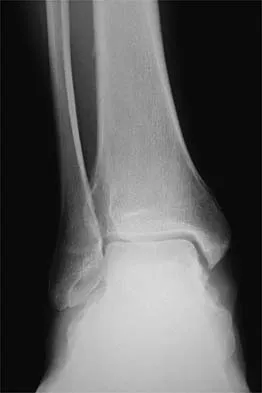

A 26-year-old ballet dancer reports posterolateral ankle pain, especially with maximal plantar flexion. Examination reveals maximal tenderness just posterior to the lateral malleolus, and symptoms are heightened with forced passive plantar flexion. Radiographs are shown in Figures 42a and 42b. What is the most likely cause of the patient's symptoms?

Explanation